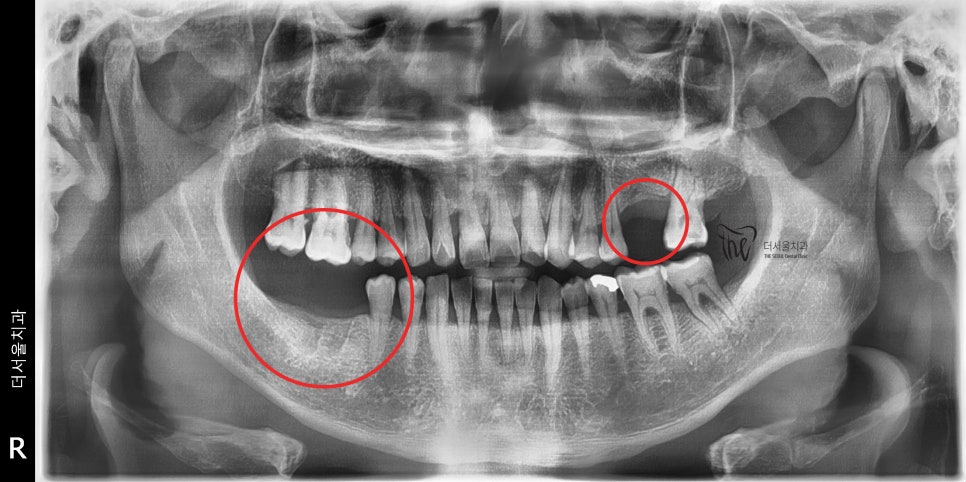

그러면서, 이 분의 엑스레이 촬영 결과를 보면

크게 2군데에서 어금니 빠짐 이 확인이 됩니다.

다행이였던 것은 아직 치아 정출이나 이동현상이

관찰이 되지 않았다는거고, 이는 어금니 빠짐 에

따라서 빠른 시일내에 치과로 오셨다는 점입니다.

이렇게 되면, 임플란트 시술을 진행을 했을 때

조금 더 유리한 점들이 많습니다.

뼈가 아직 수축을 하지 않았기 때문에,

뼈이식술을 진행하더라도 그 양이 현저히

줄어들 수 있으며 소수술의 범위가

줄어들기 때문에 체어 타임 또한 많이

감소 될 수 있는 이점이 있는거죠.